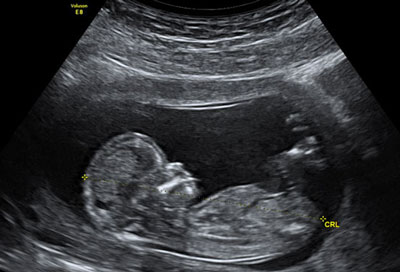

سونوگرافی تعیین جنسیت جنین

اینکه جنینی که در رحم مادر زندگی می کند پسر است یا دختر نه فقط کنجکاوی پدر و مادر بلکه اطرافیان شان را هم در طول بارداری بر می انگیزد و همه مدام از والدین جوان می پرسند که بالاخره این بچه پسر است یا دختر. از علائم بارداری که بگذریم، دقیق ترین روش برای تعیین جنسیت جنین انجام سونوگرافی است.

اگرچه روش های جدید از جمله نوعی کیت های خاص وارد بازار شده که والدین بتوانند در اولین سونوگرافی بارداری یعنی حدود 10 هفتگی به جنسیت جنین پی ببرند ولی اثربخشی این روش ها در مطالعات بلندمدت به اثبات نرسیده و هنوز هم متخصصان سونوگرافی حوالی 18 تا 20 هفتگی را برای تعیین جنسیت جنین به والدین توصیه می کنند.

بهترین زمان انجام سونوگرافی تعیین جنسیت 18 تا 20 هفتگی است. قبل از این زمان ممکن است رشد به اندازه کافی نباشد و بعد از بیست هفتگی نیز ممکن است بچه بزرگ شده و به دلیل کوچک شدن فضای رحم و فشرده بودن بدن جنین، چیز زیادی در سونوگرافی مشخص نباشد.